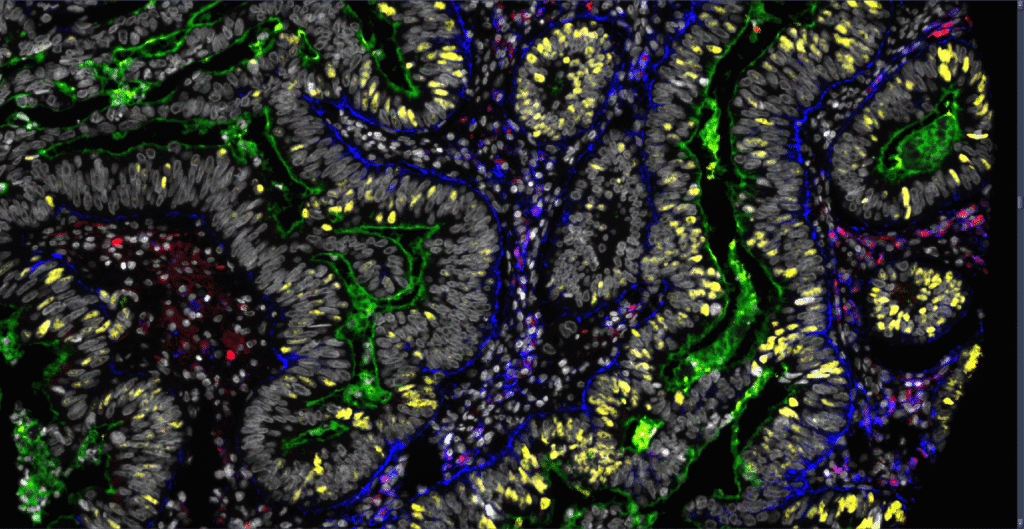

µCAN takes a cancer biopsy sample as input and combines proprietary patient-derived tumoroid culturing conditions with state of-the-art machine learning, and computer-vision guided fluorescence high- content drug screening and analysis, to identify the best therapeutical approach for clinical practice.